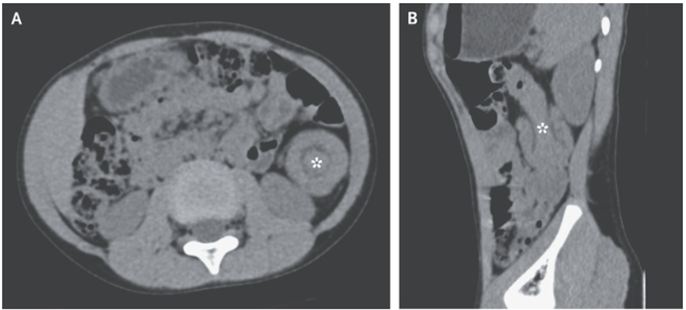

CTでは下降結腸にターゲットサイン(A:横断面、B:矢状面)が明らかにあった。

「結腸腸重積症」と診断された。